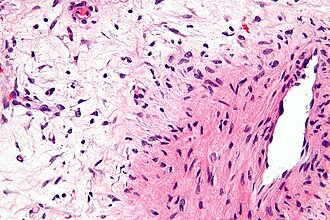

Aggressive angiomyxoma. H&E stain. | |

| LM | thick blood vessels that meld into the surrounding stroma, myxoid stroma, small stellate cells/spindle cells without significant nuclear atypia |

- Thick blood vessels that meld into the surrounding stroma - key feature.

- Myxoid stroma - key feature.

- Small stellate cell/spindle cells without significant nuclear atypia.